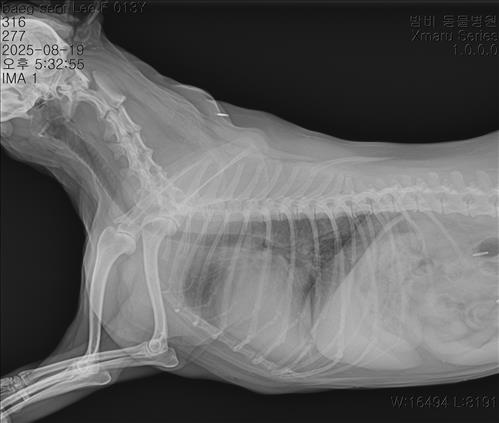

폐 부위에서 전반적으로 뿌옇게 보이는 부분이 일부 보이는데, 이는 심장비대로 인한 폐혈관 울혈일 수 있고, 폐수종이 차기 시작하는 초기 소견일 수 있습니다. 심장병 C단계로 단정하려면 폐 실질에 뚜렷한 물 번짐 패턴이 보이거나, 기침/호흡곤란/호흡수 증가같은 증상이 동반됩니다. 지금은 B2단계지만 폐울혈이 의심되는 경계 상태일 가능성이 있습니다. 더 정확히 하시려면 심장초음파 검사를 하는 것을 권해드립니다.

강심제는 B2단계부터 사용하는 것이 권장되고 이뇨제는 반드시 폐수종이 확실할 때 투여하는 것이 안전합니다. 집에서 휴식 시 호흡수 모니터링을 해주시고, 기침이 심해지거나 호흡수가 늘어나면 바로 병원에 내원하시는 것이 안전합니다.